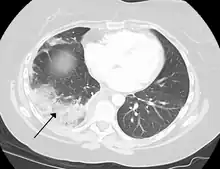

Infarction of the lung due to a pulmonary embolism

By histopathology